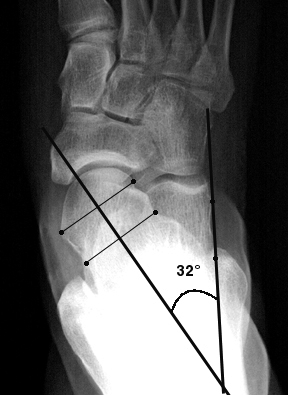

Age gender obesity cerebral palsy syndrome of down are known risk factors for the. In contrast pes valgus is a deformity characterized by the outward turning of the heel or the inversion of the foot. The disorder occurs when the distal tibial shinbone growth plate closes prematurely causing asymmetrical growth of the tibia that results in a bowlegged appearance and lameness. Varus is a latin term meaning bent inward whereas valgus is a latin that denotes being bent outward.

An example of this deformity is the pes valgus which is a deformity of the foot. Whenever the distal part is more lateral it is called valgus. Pes varus is an example of a varus deformity. A varus angulation is known as the distal part of a bony section deviates in a medial location.

Pes varus is a latin term that combines pes foot and varus inward and describes a deformity in which the distal tibia is turned inward toward the body. Pes pl. Pes adductus talipes varus.